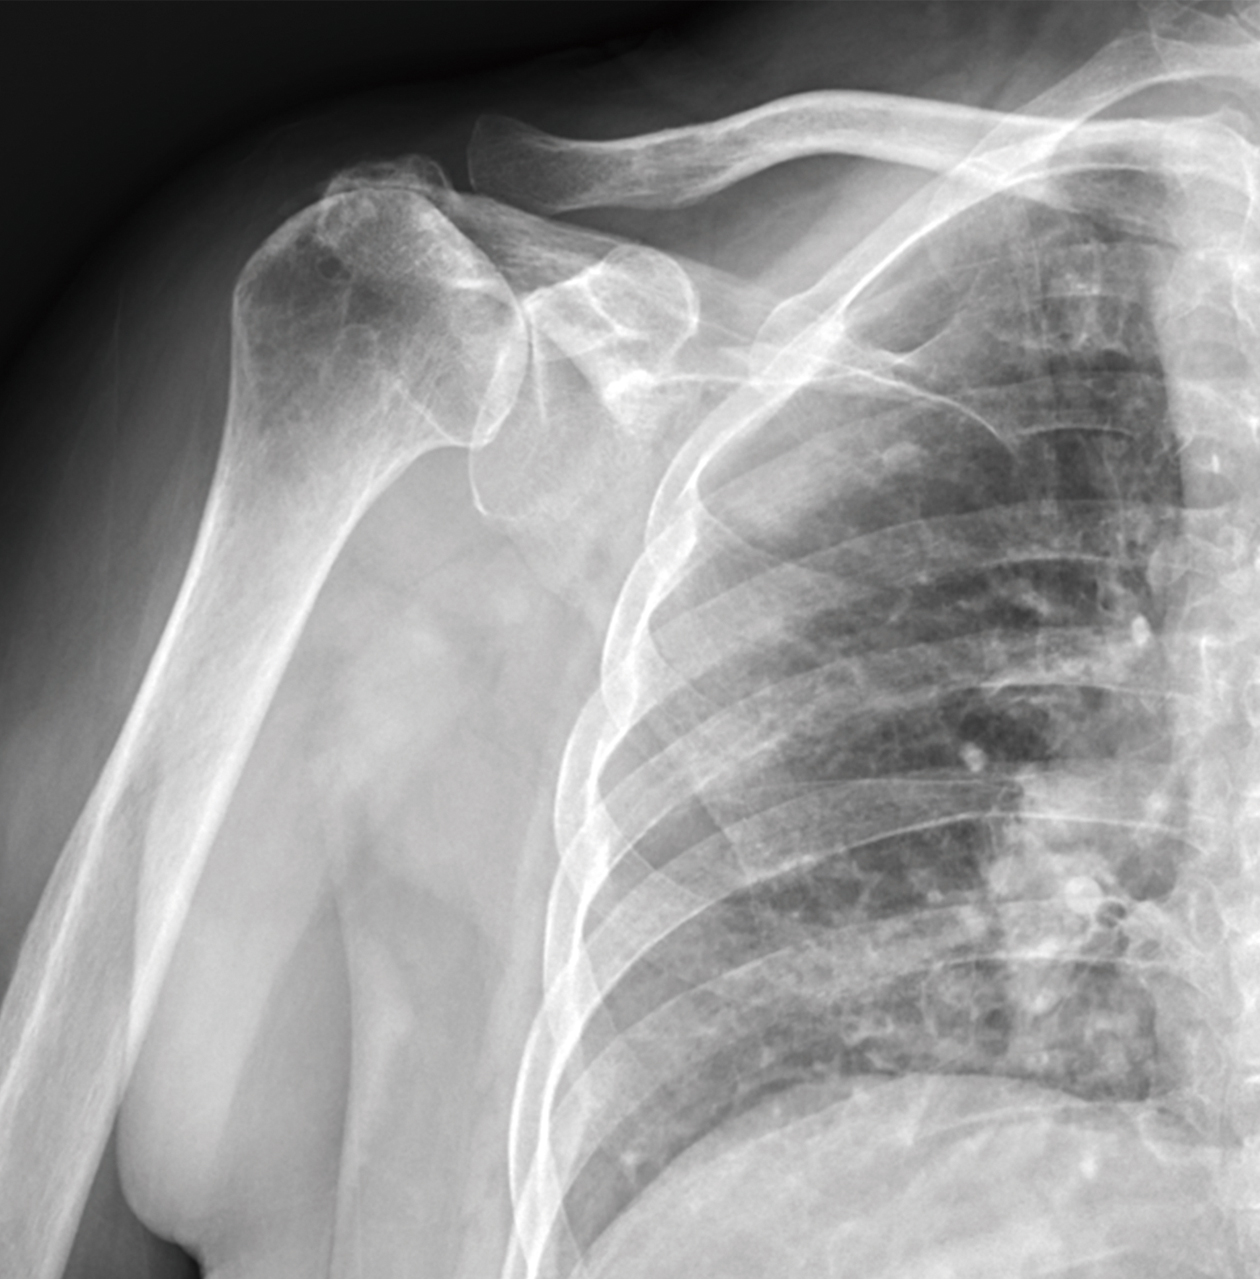

傳統人工肩關節

• 傳統解剖型人工肩關節

• 人工半肩關節